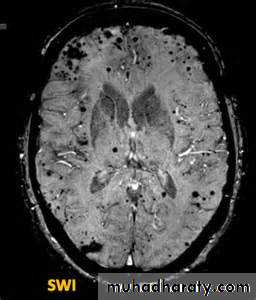

• Gradient- echo sequences are extremely sensitive to the presence of substances that cause local alterations in magnetic properties. Examples of such substances include iron-containing haemosiderin and ferritin found in chronic blood. It has known as susceptibility weighted imaging.